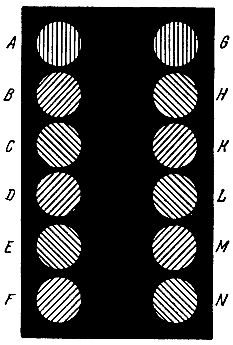

Для испытания глаз на астигматизм врачи-окулисты часто применяют специальную таблицу (рис. 10), где двенадцать кружков имеют штриховку равной толщины через одинаковые интервалы.

Рис. 10. Фигура для определения степени и меры астигматизма глаза.

Глаз, обладающий астигматизмом, увидит линии одного или нескольких кружков более черными. Направление этих более черных линий позволяет сделать вывод о характере астигматизма глаза.